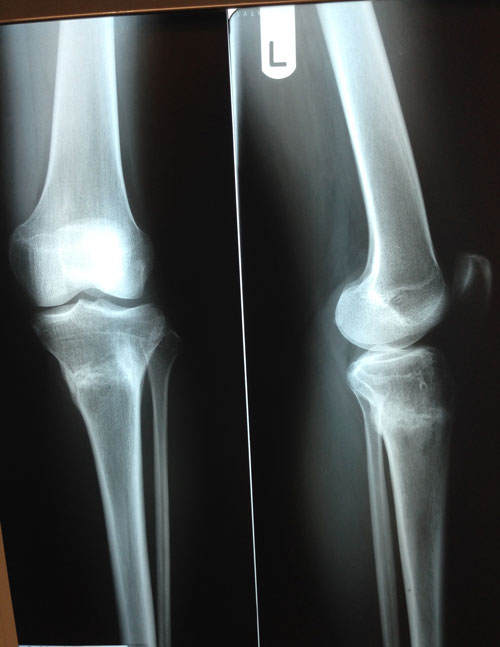

Дата снятия аппаратов 06.11.02013г.

Срок лечения 107 дней.